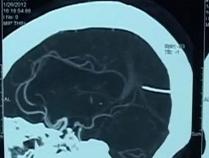

三岁男孩腹部凸起,医生检查发现在他的胃中居然有未成形的胎儿,也就是所谓的寄生双胞胎。